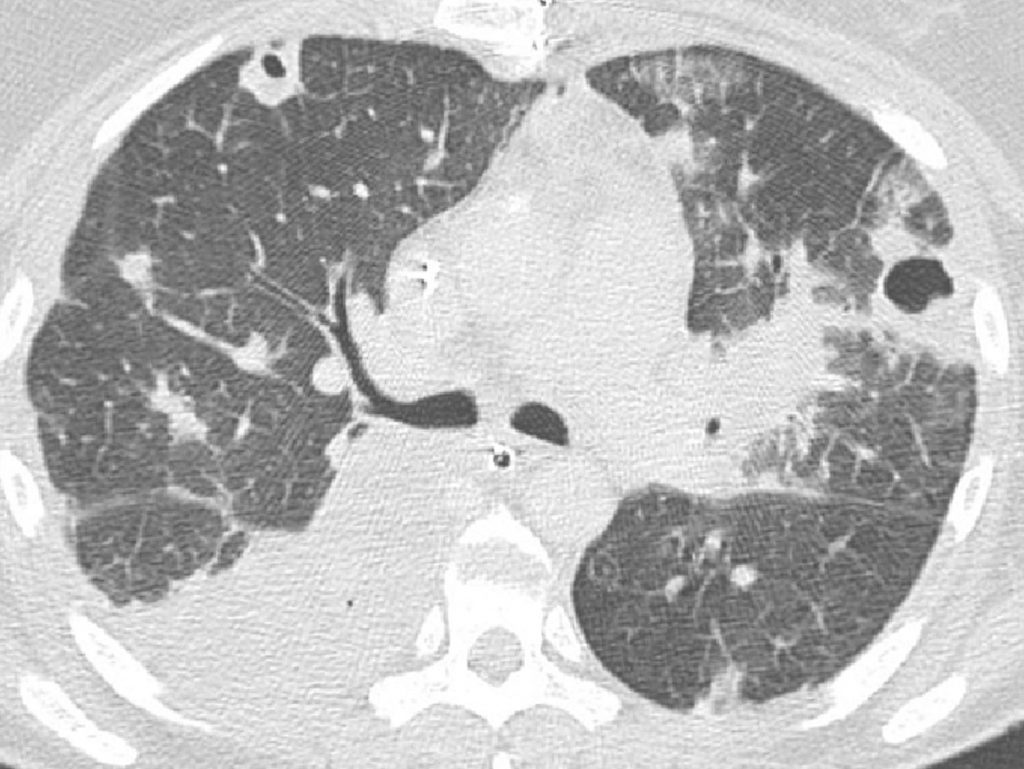

La tomodensitométrie permet de voir des condensations de petite taille et des plages en « verre dépoli » peu ou pas visibles en radiographie. Elle est plus performante pour analyser le caractère cavitaire d’un foyer infectieux, ce qui peut orienter vers certains agents microbiens spécifiques (figure 96.3), et pour rechercher des complications : abcès pulmonaire ou empyème pleural (cf. figure 91.3).

Fig. 96.3. Scanner thoracique.

Foyer de condensation du segment apical du lobe inférieur droit et multiples nodules pulmonaires, pour certains excavés, correspondant à des abcès à staphylocoques compliquant une endocardite tricuspidienne chez une patiente toxicomane IV.

Source : CERF, CNEBMN, 2022.